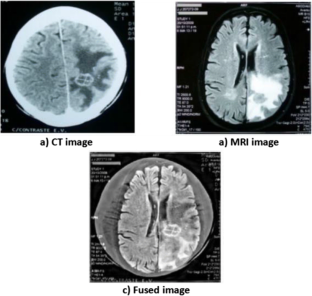

Fig. 1